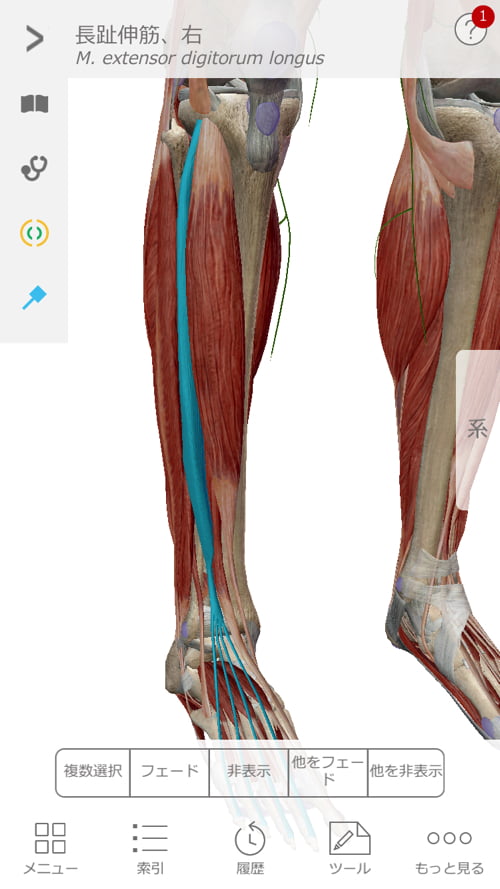

施術はまず足首から足の甲、そして膝へ繋がるこれらの筋肉や腱を調え直しました。

図で分かるように足の甲から膝へ、足裏から膝へと繋がっています。

そして膝から上は腰骨に繋がっているので、膝は足首にも腰にも影響があるのです。